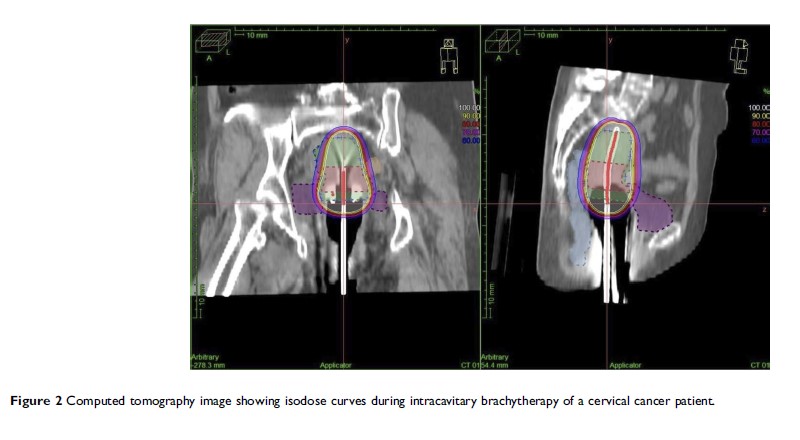

膀胱体积对宫颈癌患者放疗计划及临床疗效的影响